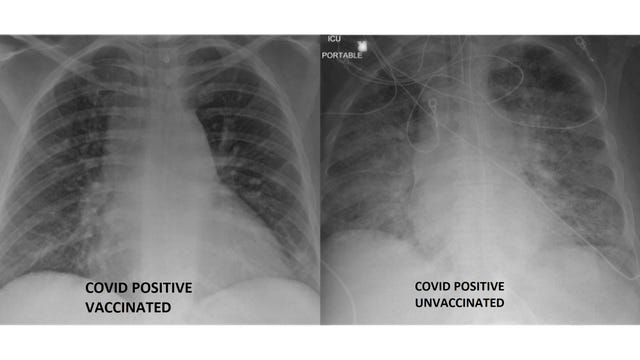

COVID-19 lung X-rays show difference between vaccinated, unvaccinated patients

A hospital shared lung X-rays of vaccinated and unvaccinated COVID-19 patients in an effort to show the vaccine’s effectiveness at preventing severe illness.